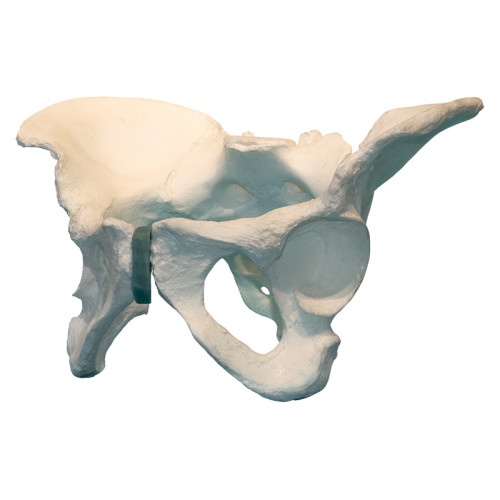

Композитная модель таза

Композитная модель таза

Описание

Модель представляет точную анатомическую копию таза человека. Путем подбора полимерных материалов механические свойства изделия (вес, плотность, упругость) максимально приближены к естественным прижизненным значениям.

- Для изучения анатомического строения осевого скелета человека.

- Для отработки навыков механических манипуляций на кости, применяемых в травматологии.

- Для воспроизведения переломов кости с последующим воссозданием структурной целостности посредством учебных операций.